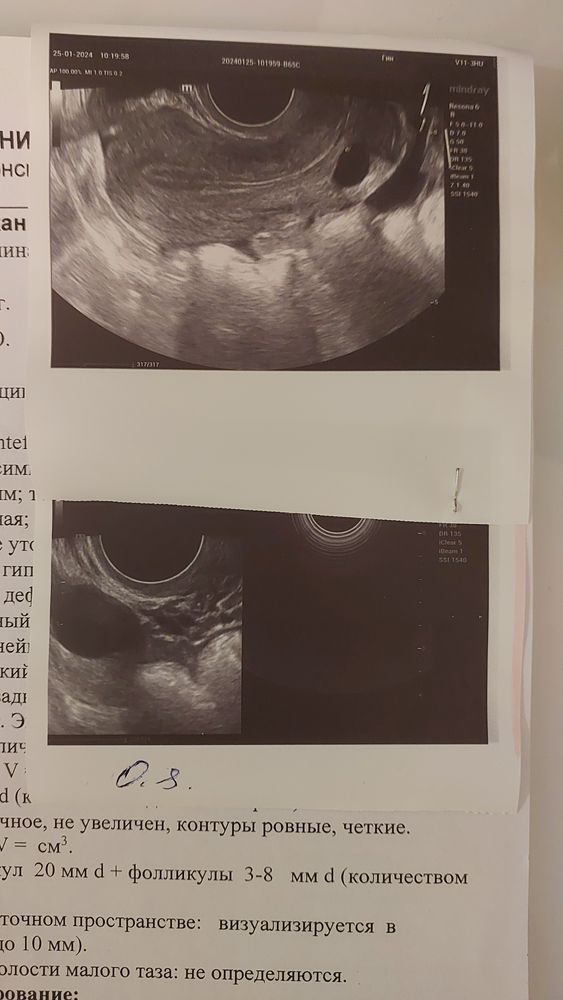

Узи на 11 ДЦ. ДФ 20 мм. В ожидании овули

Когда ждать овуляцию. Думаю сходить на фоликулометрию в субботу посмотреть. Что думаете? Точно должен лопнуть? В итоге в МИД был один фолик и почти нет шансов на еств. бер. А по факту у меня помимо ДФ ещё 10 антральных фоликулов и правый яичник рабочий. Эндометрий уже 10 мм. По результатаи ГСГ трубы проходимы. Переживаю на счёт кисты в шейке. Гинеколог моя сказала это не влияет на зачатие. Назначила кровь на биохимию и гормоны 2 фазы. Пойду сдавать на 20 дц (должно быть 7дпо). Будет потом по факту назначать препараты для нормализации горм. фона и поддержки. Пью циклодинон и авариамин и ещё кучу витамин. Жаль в этом цикле муж на вахте и только в след. будем пробовать.

Сходила в субботу (13 ДЦ) на узи (фолликулометрию) овуляция как раз была видимо ночью, так как вечером страшно тянули стреляли яичники. Эндометрий 10.5 мм. В эту субботу пойду сдам гормоны лютеиновой фазы и биохим анализ крови. Узи думаю вот тоже сделать посмотреть жёлтое тело